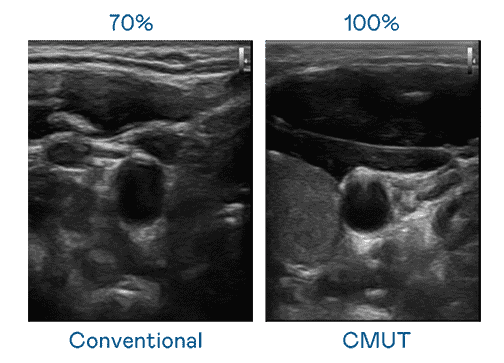

CMUT 技术是一种用电容式微机电元件来产生超音波讯号的技术。。与传统 PZT 压电式技术相比,,,CMUT 频宽增加 30%,,更宽频的超音波讯号让影像解析度大幅提升,,,,是实现高影像品质医疗超音波扫描、、、、促进精准医疗发展的关键技术。。

大频宽带来超清晰影像

超音波影像的解析度高低,,,,首先取决于探头能发出的讯号频宽。。壹号平台 CMUT 可提供高清晰的超音波讯号,,提供高频宽、、、、高灵敏度、、、影像纹理细节更高的超音波影像,,,,协助医护人员缩短影像判读时间及利用精准的医疗影像进行诊断。。。。